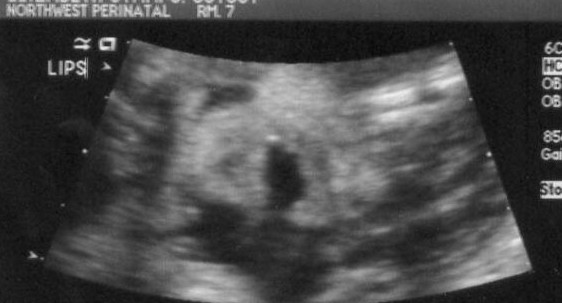

Here is one of his lower face (sideways). The mouth is open and the nostrils of his nose are clearly visible. How fun is that?

This was a fun view - the bottom part of the baby's face! Here we can see his chin, mouth and nose.